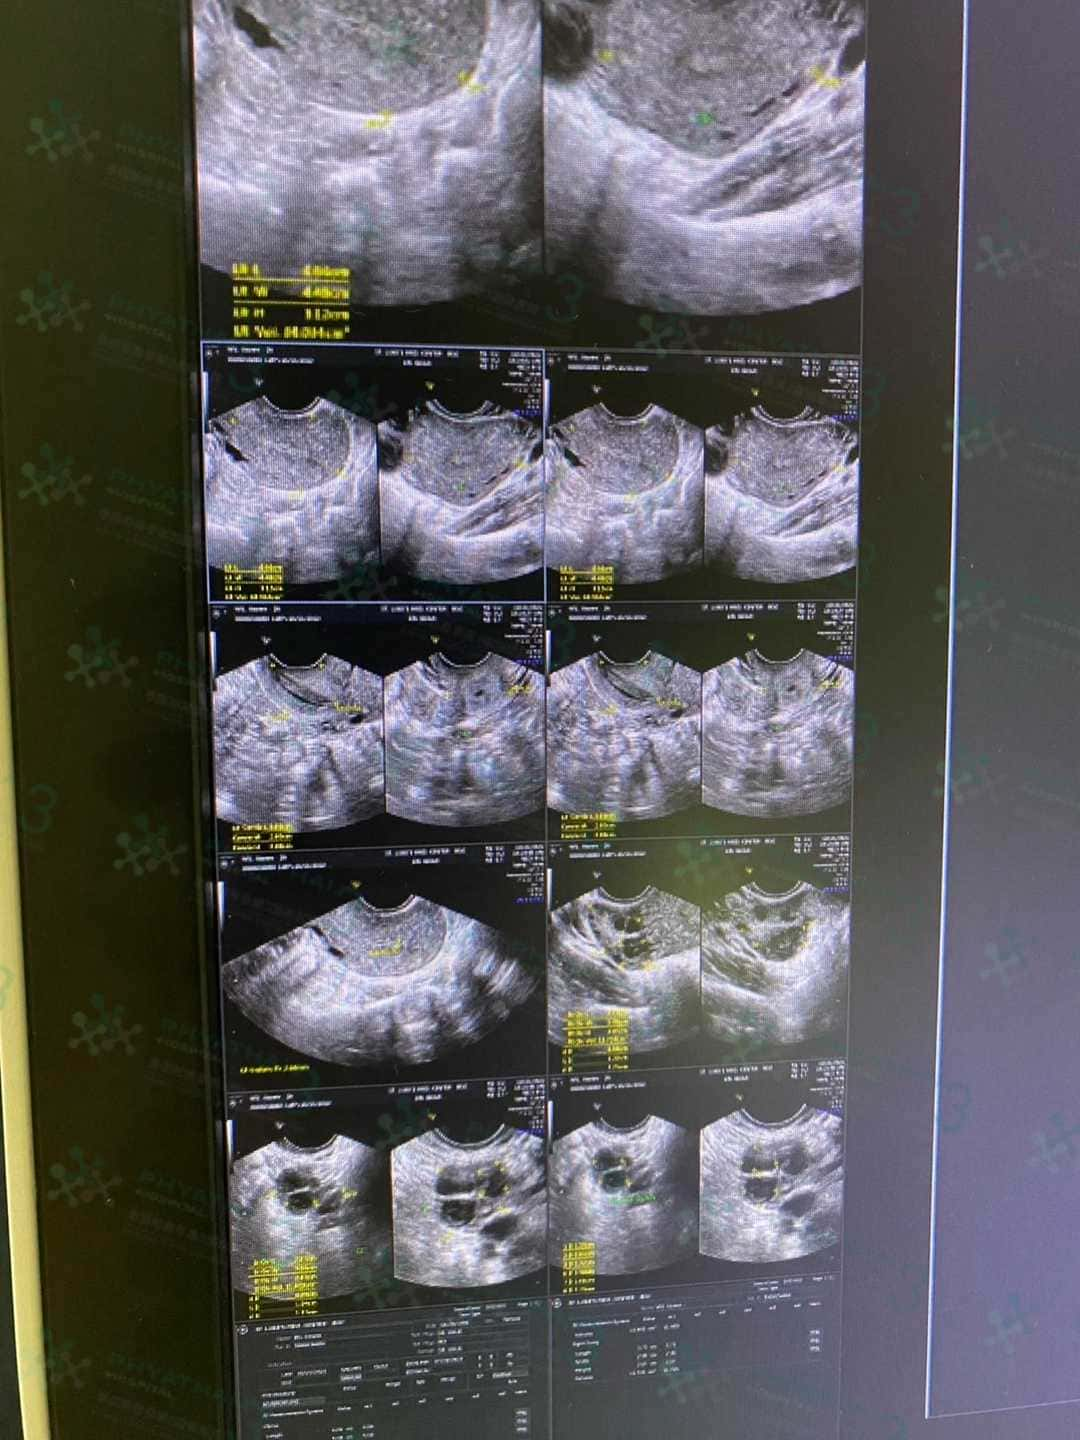

由于疫情开放了,所以很多试管姐妹也会尽量减少在泰国停留的时间,那同事也有很多患者疑问,如果我们取卵后就回去了,那么用药或者检查应该怎么办呢,其实不用太过担心这个问题,因为我们全程都有医疗翻译和医生进行跟踪,月经第二天去检查是否有空卵泡,马上把报告发给医生完全没问题,医生也会通过报告给患者进行远程用药以及检查的指导,让您没有后顾之忧!所以试管姐妹们取卵完大可以放放心心回家喔